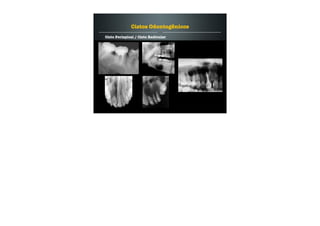

Cisto Periapical / Cisto Radicular

Cisto formado associado a um ápice dental de um dente

necrosado presumivelmente. Resposta inflamatória.

Cisto radicular lateral ou cisto periapical lateral.

Crescimento lento e assintomático.

Cisto odontogênico mais comum - 65%.

Cistos Odontogênicos